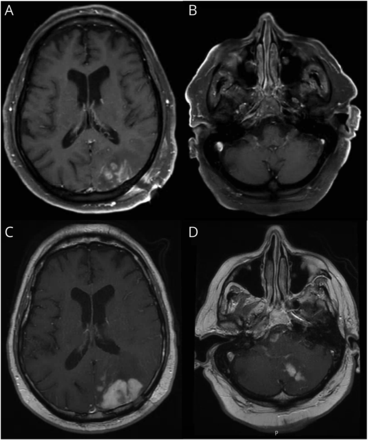

大脑的核磁共振显示间隔增大枕叶和小脑病变,以及新的提高桥的损伤(图1)。脊柱MRI显示没有异常的帘线增强。血管造影显示,没有证据表明血管炎先生。没有证据表明身体原发恶性肿瘤的CT扫描或睾丸超声波。